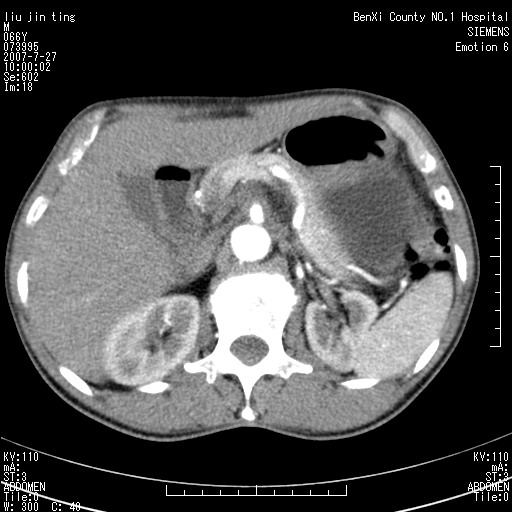

腹痛,背痛,无恶心呕吐,不黄,彩超示胰腺钩癌,ct扫描病灶平扫30-40hu,增强后动脉期40--60hu,静脉期50-68hu,真的是钩突上的么?您要试一试么?

沿着肠系膜上动脉呈匍匐性生长的软组织肿块,形态不规则,包绕肠系膜上动脉,呈明显强化,考虑来源于肠系膜的恶性肿瘤

肠系膜根部肿块,累及肠系膜上动脉,考虑肿大淋巴结累及肠系膜上动脉.

沿着肠系膜上动脉呈匍匐性生长的软组织肿块,形态不规则,包绕肠系膜上动脉,呈轻-中度强化,考虑来源于肠系膜的恶性肿瘤。

钩突是正常的,只见腹膜后淋巴结的肿大,考虑淋巴瘤或转移可能。

支持!恶性纤维组织细胞瘤可能,与淋巴瘤及淋巴结转移鉴别(腹主动脉周围清晰,其他部位亦未见明显肿大淋巴结)。